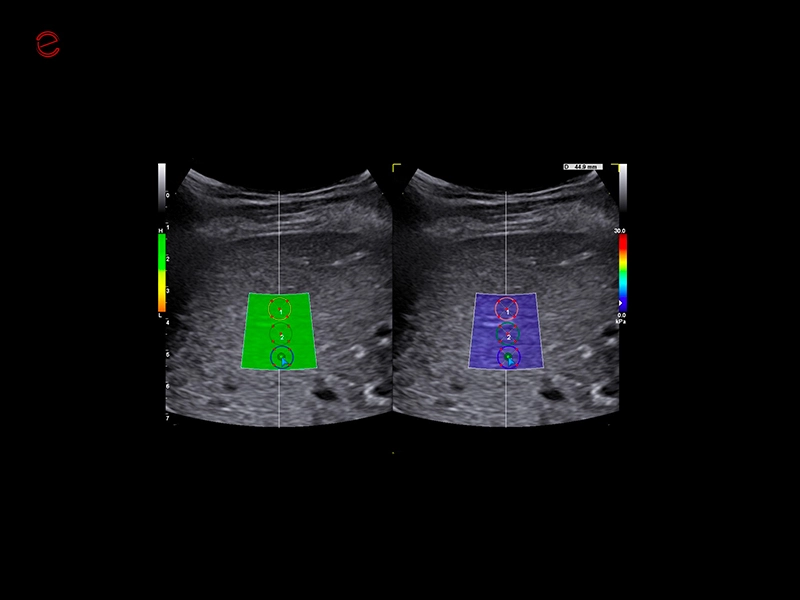

The MyLab™C30 compact ultrasound machine is specifically designed to meet the demands of everyday clinical practice for fast ultrasound access, versatility of use, and space constraints. All this has been achieved without compromising image quality and ultrasound performance. By sharing advanced imaging technologies and transducers with our high-end systems, the MyLab™C30 delivers high quality images and clinical information in a truly compact ultrasound device.

Elevated performance for enhanced diagnostic insights

Featuring the ClearWave Architecture, which combines Esaote’s advanced XBeamforming and XSmart Postprocessing technologies, the MyLab™C30 incorporates state-of-the-art imaging technologies to set a new standard for image quality, giving professionals diagnostic confidence wherever they need it. Maximize the performance of the MyLab™C30 with its wide range of probes for all clinical needs, from daily routine to the most advanced expectations. Equipped with a wide range of advanced features and an accelerated workflow powered by Artificial Intelligence, the MyLab™C30 is your portable ultrasound device that knows no boundaries.